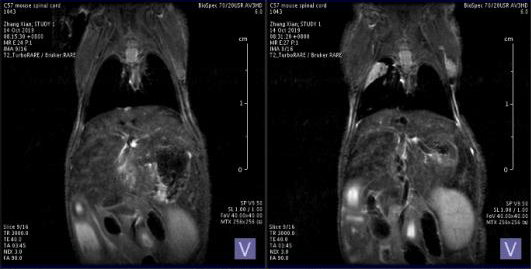

第三:小动物核磁。小动物核磁技术可以更明细那地观察到肿瘤细胞在肝脏,肺脏或者其他器官的转移情况